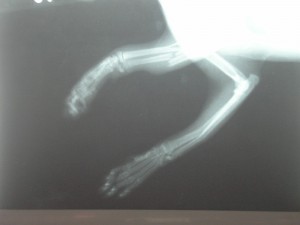

Sisi byla nalezena 29.03.2006 na sídlišti s polámanými předními

packami. Utrpěla

fraktury obou předních končetin, z nichž jedna byla tříštivá fraktura loketní

a vřetenní kosti, došlo také ke zdevastování měkké tkáně.

Dne 30.03.2006 se Sisi podrobila operaci, při které byla provedena osteosyntéza, kdy se tato těžká zlomenina fixovala šrouby. Druhou frakturu

fixuje termoplastická dlaha. Sisi se po této těžké operaci velice dobře